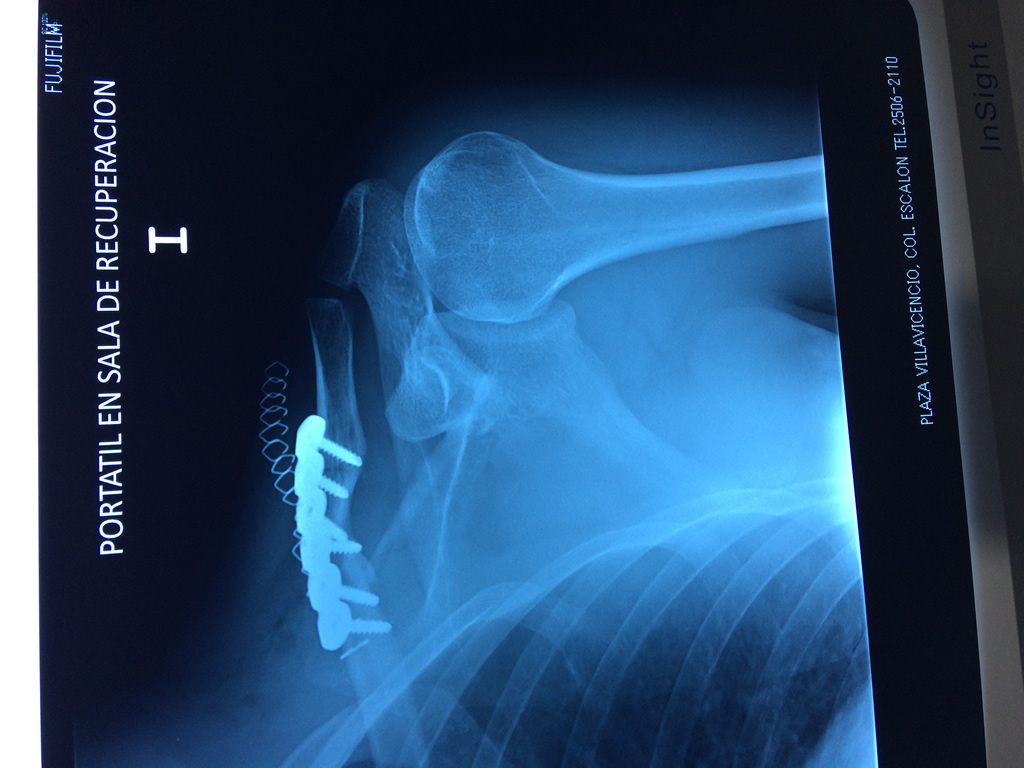

Clavicula 4

Detail Download